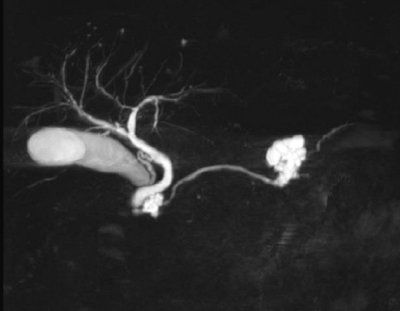

血液所見:赤血球 480 万、Hb 15.8 g/dL、Ht 46 %、白血球 6,800、血小板 24 万。血液生化学所見:アルブミン 4.3 g/dL、AST 32 U/L、ALT 40 U/L、LD 180 U/L(基準 176〜353)、ALP 212 U/L(基準 115〜359)、γ-GTP 40 U/L (基準 8〜50)、アミラーゼ 73 U/L(基準 37〜160)、CEA 3.2 ng/mL(基準 5.0 以下)、CA19-9 14 U/mL(基準 37 以下)。CRP 0.2 mg/dL。腹部造影CTとMRCP とを示す。